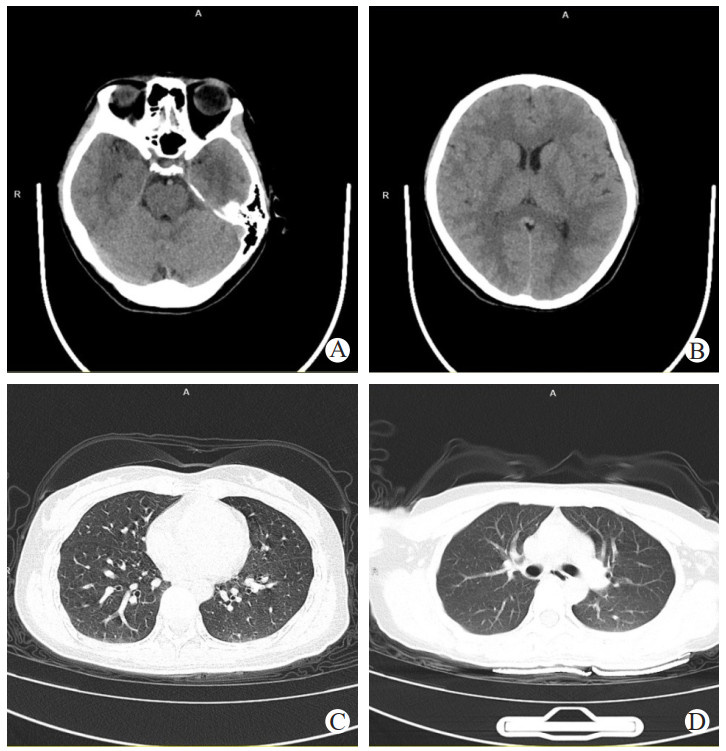

患者病情进展极快,召集全院讨论后考虑诊断为“感染后急性坏死性脑病”,予临时加用甲泼尼龙500 mg ivgtt once大剂量冲击、人免疫球蛋白20 g ivgtt qd、美罗培南针2 g ivgtt q8h、复方甘草酸苷60 mL ivgtt qd、谷胱甘肽1.2 g ivgtt qd,并启用连续性肾脏替代治疗(continuous renal replacement therapy, CRRT)消除炎性因子治疗【模式:CVVHDF,滤器:百希瑞Oxiris(百特医疗用品贸易上海有限公司),处方:血流量:150 mL/min,置换量:1 200 mL/h(前稀释),透析液:1 500 mL/h,脱水量:150 mL/h】。16:53患者出现双眼向左凝视,牙关紧闭,四肢肌张力增高,四肢抖动,予镇静治疗、气管插管机械通气保持气道通畅。18:40患者出现双侧瞳孔散大,考虑为脑疝,立即予复查CT(见图 3)提示:两侧大脑半球白质、小脑及脑干多发低密度灶、脑肿胀。患者家属要求转上级医院进一步治疗,转入浙江大学附属邵逸夫医院治疗。

注:A、B为颅脑CT影像,两侧大脑半球白质、小脑及脑干多发低密度灶、脑肿胀,脑炎;C、D为胸部CT影像,提示两肺感染 图 3 3月22日患者颅脑、胸部CT

3月24日,患者昏迷,气管插管机械通气状态,GCS评分E1VTM1=3分,回嘉兴一院抢救室救治,复查CT(见图 7)提示:两侧大脑半球白质、小脑及脑干见多发斑片状低密度影,脑实质肿胀。脑室系统及脑沟、脑池变浅。患者预后极差,患者家属决定放弃治疗、回家,最终患者死亡。患者病情进展总结见图 8

注:提示两侧大脑半球白质、小脑及脑干多发斑片状低密度影,脑实质肿胀,脑炎,脑室系统及脑沟、脑池变浅 图 7 3月24日患者颅脑align="center"